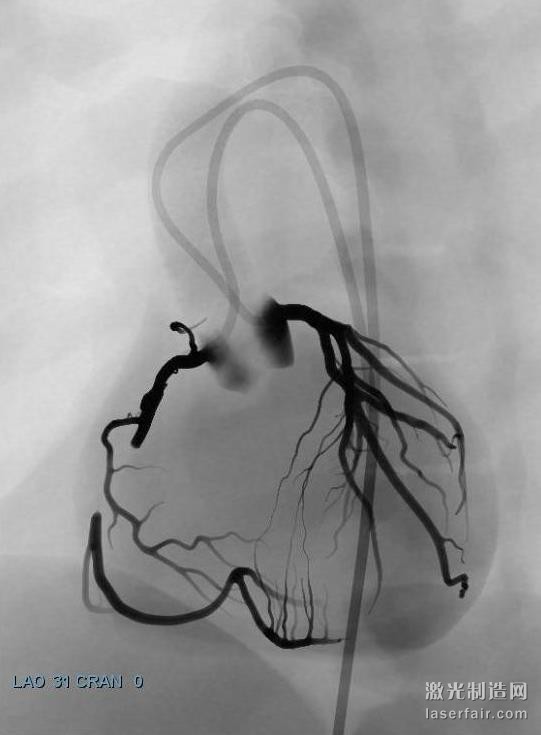

據(jù)了解,當前在介入心臟病學領(lǐng)域出現(xiàn)了重要的新進展,意味著更多的患者可以通過經(jīng)皮冠狀動脈介入(PCI)技術(shù)來治療,該技術(shù)比其它心臟手術(shù)的侵略性更小。然而,每一個重要的技術(shù)發(fā)展,都意味著心臟病專家需要學習新的技術(shù),顯然光看說明書是不夠的。為了向有經(jīng)驗的心臟病專家提供關(guān)于這些新技術(shù)的培訓,3DS開發(fā)的虛擬現(xiàn)實訓練場景可以在其 ANGIO Mentor血管腔內(nèi)模擬器上使用。這些特定的場景包括冠狀動脈CTO(慢性完全閉塞)治療和冠狀動脈分叉例等。

關(guān)于慢性完全閉塞(CTO)病變的先進的冠狀動脈介入治療場景(使用ANGIO Mentor模擬器)